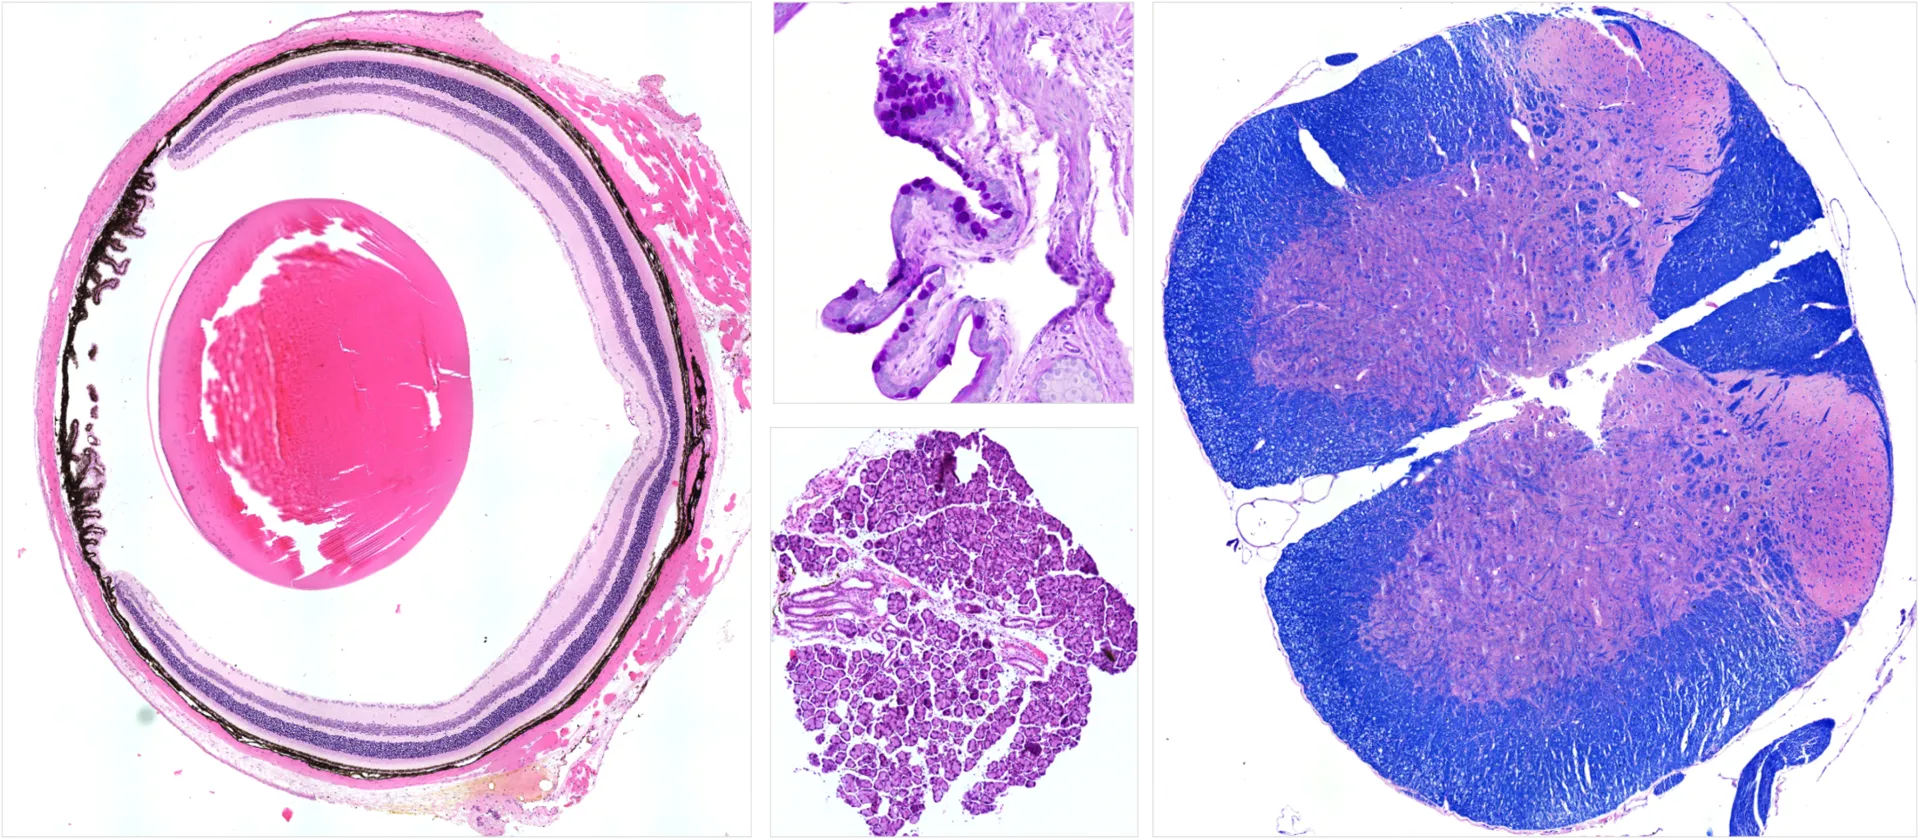

Histological staining

We routinely perform histological stains such as hematoxylin and eosin (H&E), Periodic acid-Schiff (PAS), Luxol fast blue (LFB), silver staining. For other stainings or specific staining requirements, please contact our customer service team.